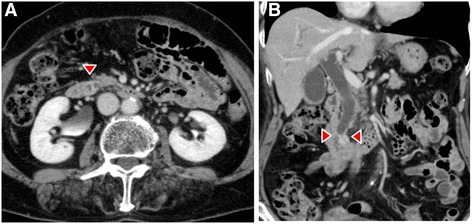

Dynamic computed tomography (CT) showed bile duct wall thickening that was enhanced in the lower part of the CBD (Fig. 2). Endoscopic retrograde cholangiography (ERC) demonstrated abrupt obstruction of the lower CBD (Fig. 3). Histological examination of biopsy specimens from the lower CBD showed adenocarcinoma with signet-ring cells. We diagnosed extrahepatic cholangiocarcinoma and performed subtotal stomach-preserving pancreaticoduodenectomy (SSPPD). The surgery lasted 348 min, and the total blood loss was 525 mL. Histopathology report suggested atypical epithelial cells exhibiting infiltrative growth, with fibrosis of the duodenal papilla (Fig. 4c). Tumor cells displayed intracytoplasmic mucus deposition, crescent-shaped nucleoli (Fig. 4d, e) extensions along the lower CBD, and invasion of pancreatic parenchyma (3 mm). AcbBd, exposed protruded type, 22 × 16 mm, por2/sig, pT3a, sci, INFc, ly1, v1, ne1, pN0, pHM0, pPM0, pEM0, PV0, A0, R0, pStage IIA according to the Japanese Classification on Cancer of the biliary tract [ref. 2] and pT3N0M0 stage IIA in accordance with Union for Internationatinal Cancer Control, 7th edition. The final diagnosis was poorly differentiated adenocarcinoma with signet-ring cell of DPC. The patient developed pancreatic fistula postoperatively (ISGPF grade B), with no other complications and was discharged on day 37 postsurgery. She has remained disease-free for 5 years since the surgery.